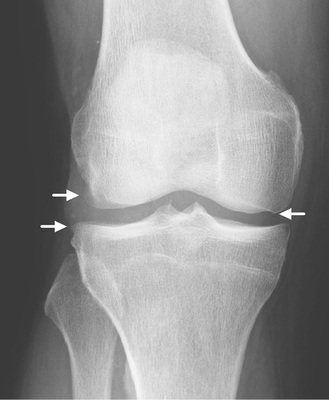

Röntgenologische Bildbefunde

Liegt eine Arthrose vor, lassen sich 4 typische Befunde in unterschiedlicher Ausprägung je nach Stadium abgrenzen:

• Gelenkspaltverschmälerung, meist asymmetrisch, betont im last-tragenden Bereich. Diese entspricht der indirekten Beurteilung der noch erhaltenen Knorpeldicke. Es muss berücksichtigt werden, dass auch eine Höhenminderung der Menisci zu einer Reduktion des Gelenkspalts führen kann;

• subchondrale Sklerosierung, betont im lasttragenden Bereich;

• osteophytäre Anbauten;

• Geröllzysten.

Je nach Aktivitätsgrad können ein Gelenkerguss, aber auch Gelenkdestruktionen vorliegen.

Röntgenologische Graduierung der Gonarthrose

Der Arthrosegrad wird klassischerweise nach Kellgren und Lawrence eingestuft (  Tabelle 1 , Beispiele   Abb. 1–4 ) (Kellgren u. Lawrence 1957). Dieser basiert auf den oben beschriebenen radiologischen Arthrosezeichen, wurde 1957 erstmals publiziert und 1963 als Bildatlas für alle Gelenke herausgegeben, um die Graduierung zu erleichtern.